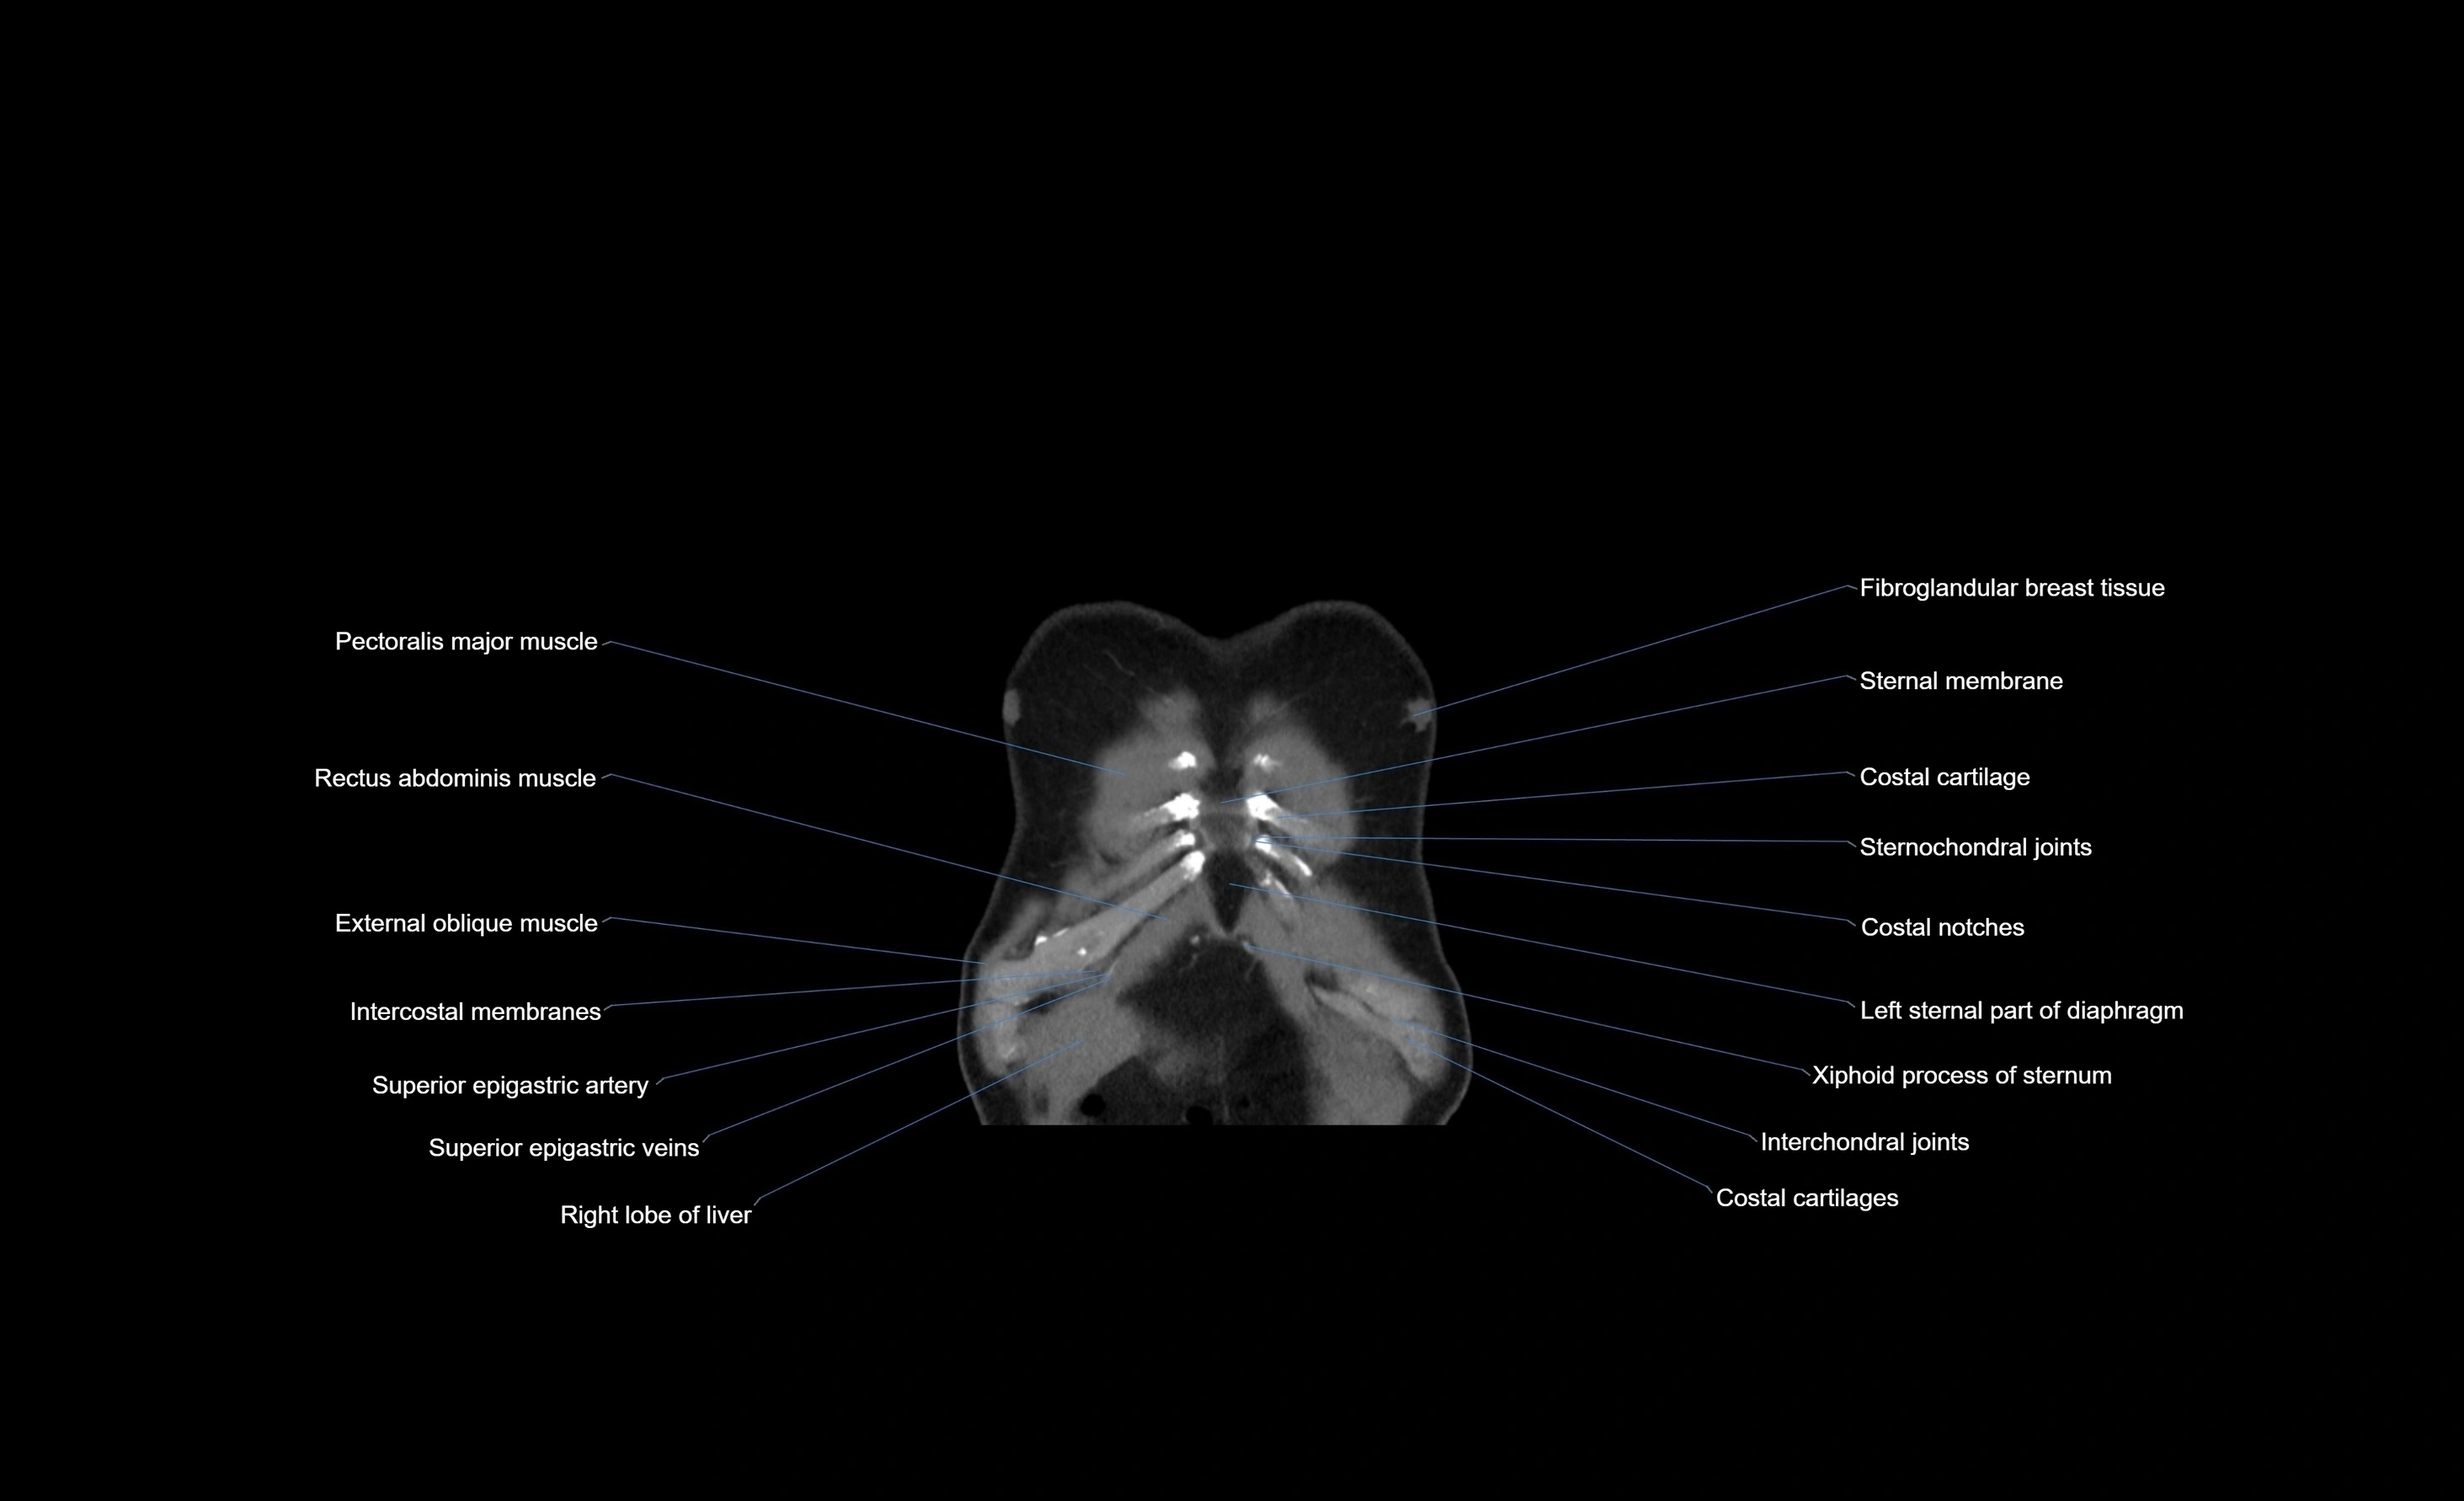

- Costal cartilages

- Costal notches

- Costoxiphoid ligaments

- Rectus abdominis muscle

- Superior epigastric artery

- Superior epigastric veins

- Xiphoid process of sternum